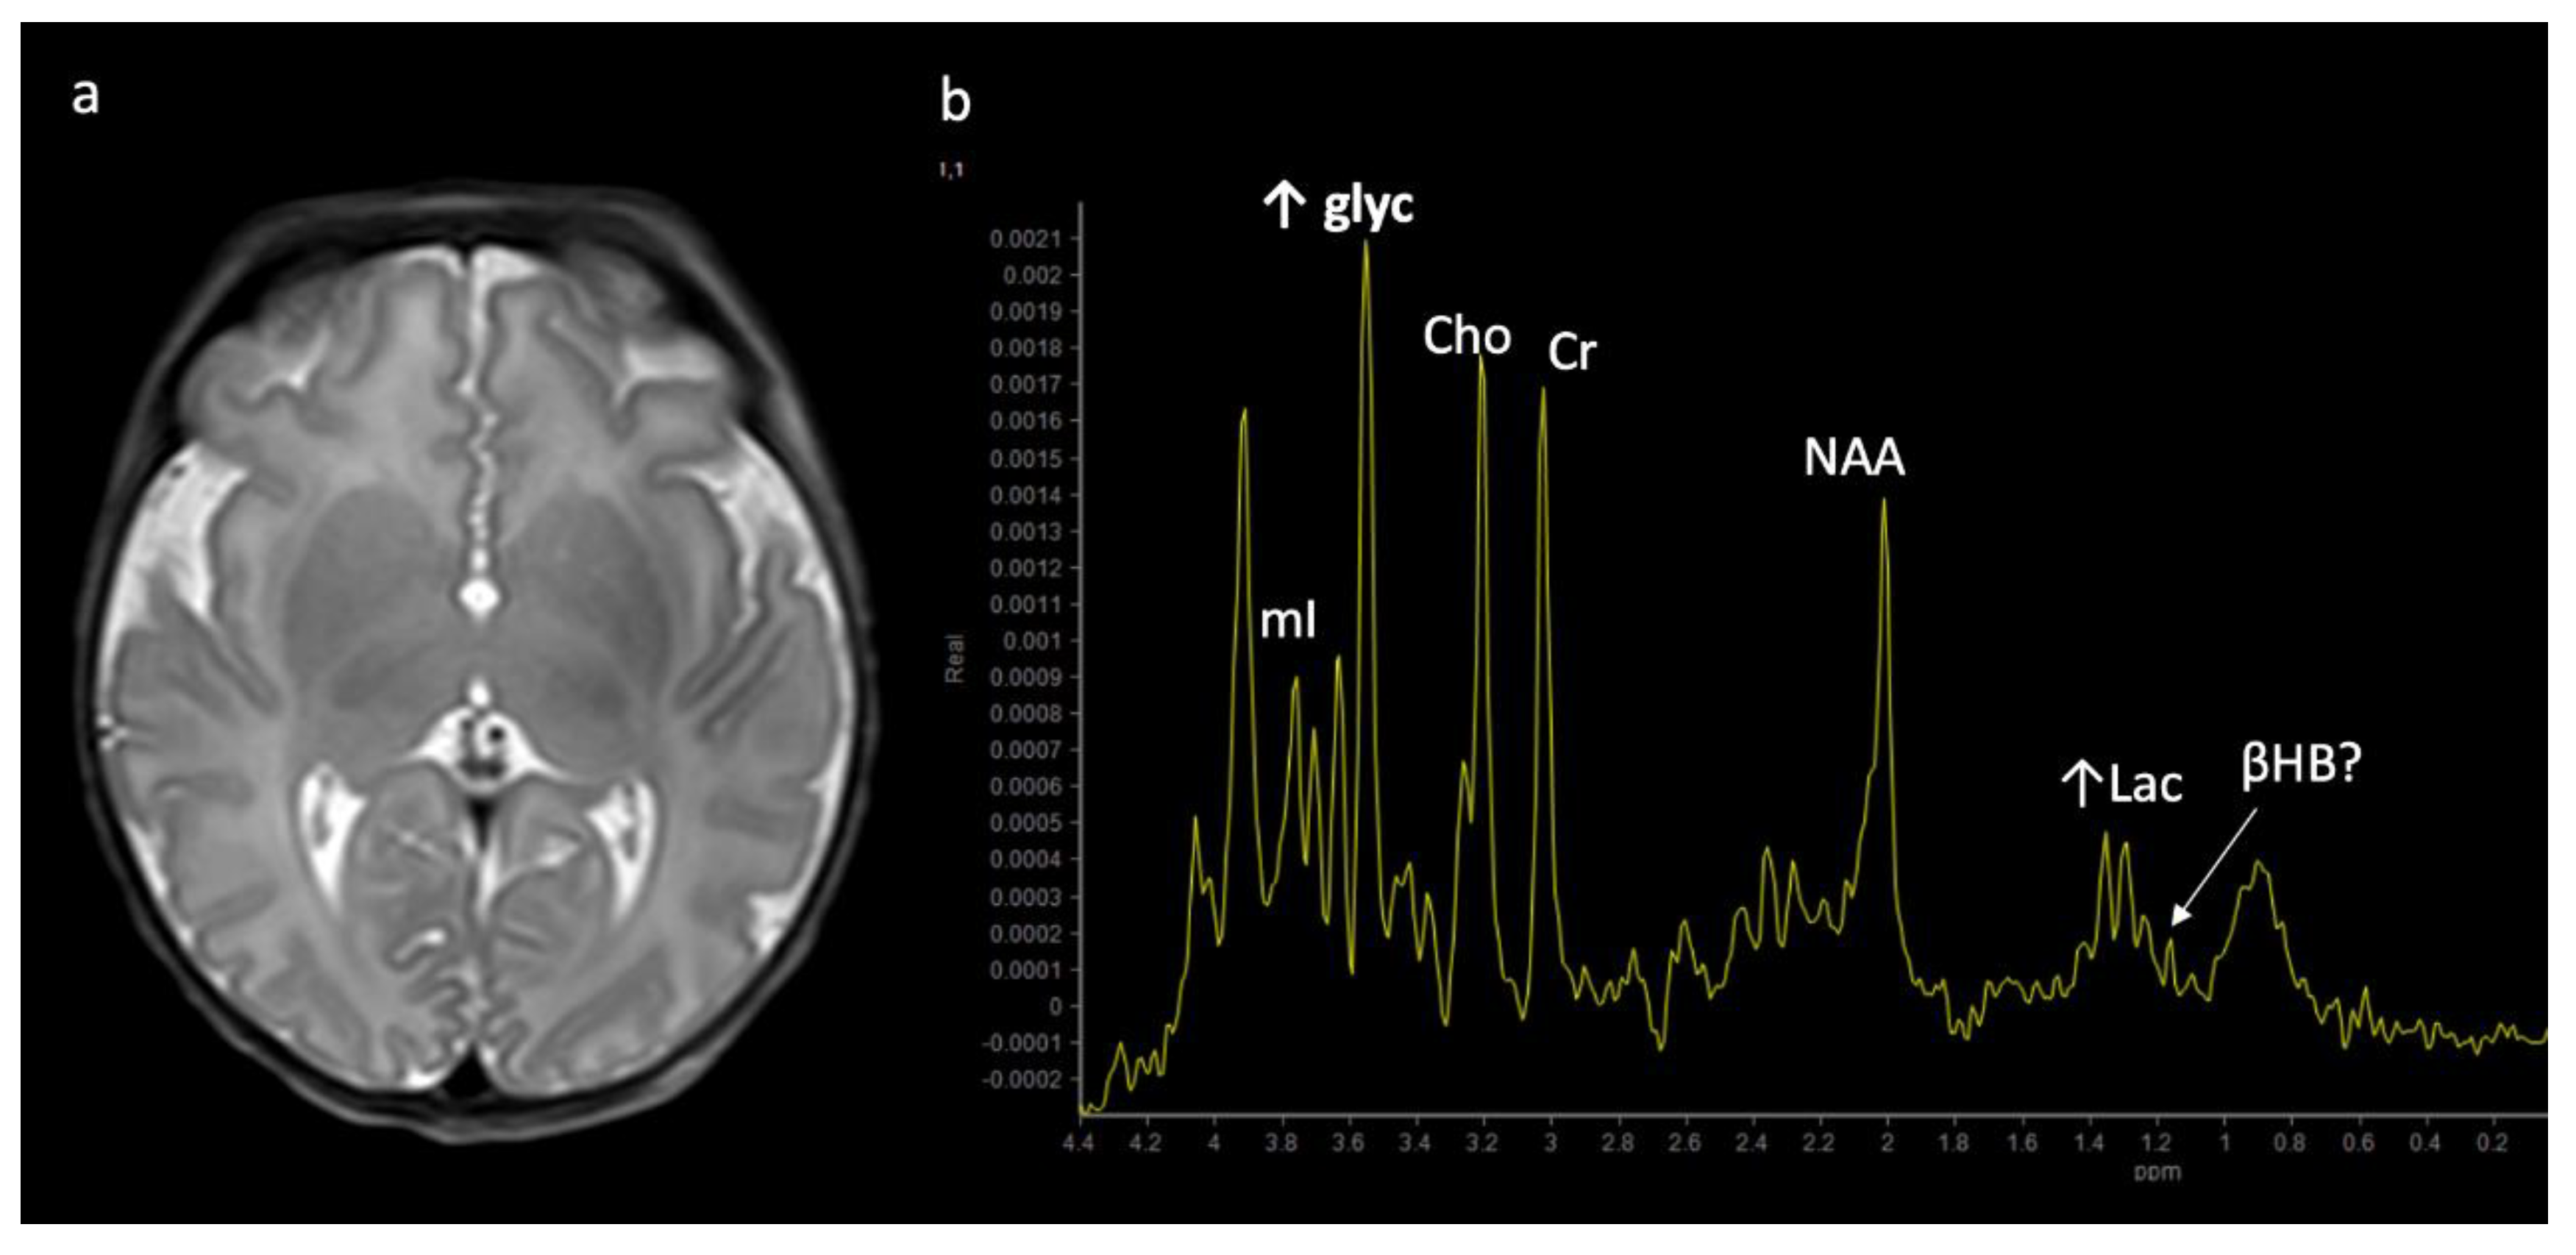

Nonketotic Hyperglycinemia (NKH) or glycine encephalopathy (Figure 9): NKH shows reduced diffusion in myelinated white matter tracts due to intramyelinic edema and vacuolization (usually involving the internal capsules, brainstem, and cerebellar white matter), with extent of involvement less prominent compared to MSUD [3,4,7,8,9]. Additional findings usually include hypogenesis of the corpus callosum and hypoplasia of the cerebellar vermis [7]. MRS reveals an elevated glycine peak at 3.55 ppm, which is best distinguished from the normal mI peak with intermediate or long echo 1H MRS due to its longer T2 decay [3,7,8].

Figure 9.

Two-week-old with seizure activity found to have nonketotic hyperglycinemia (NKH). (a) Axial T2WI at the level of the basal ganglia shows lack of normal myelination related hypointensity in the posterior limbs of the internal capsules. (b) SV-MRS over the left basal ganglia reveals a large glycine (gly) peak at 3.55 ppm (confirmed on longer TE MRS, not shown), mild Lac, mildly reduced NAA and Cho, and possible beta hydroxybutyrate (βHB) from ketosis at 1.18 ppm.